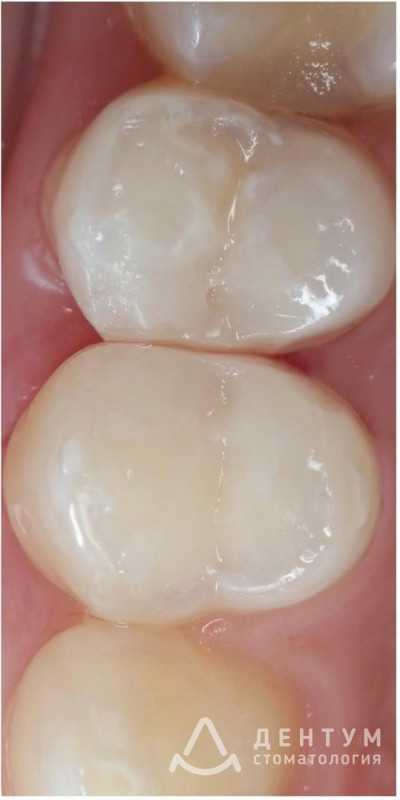

4 работы в портфолио